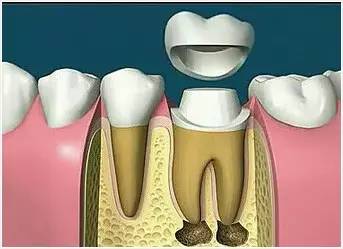

8、完成牙體修復(fù)

X線片顯示根管充填完好,行暫時或永久牙體修復(fù),帶上牙冠,保護(hù)患牙。至此根管治療才可算完成,同時根管治療后還需復(fù)診,一般周期可為3個月、半年、1年、2年或更長。